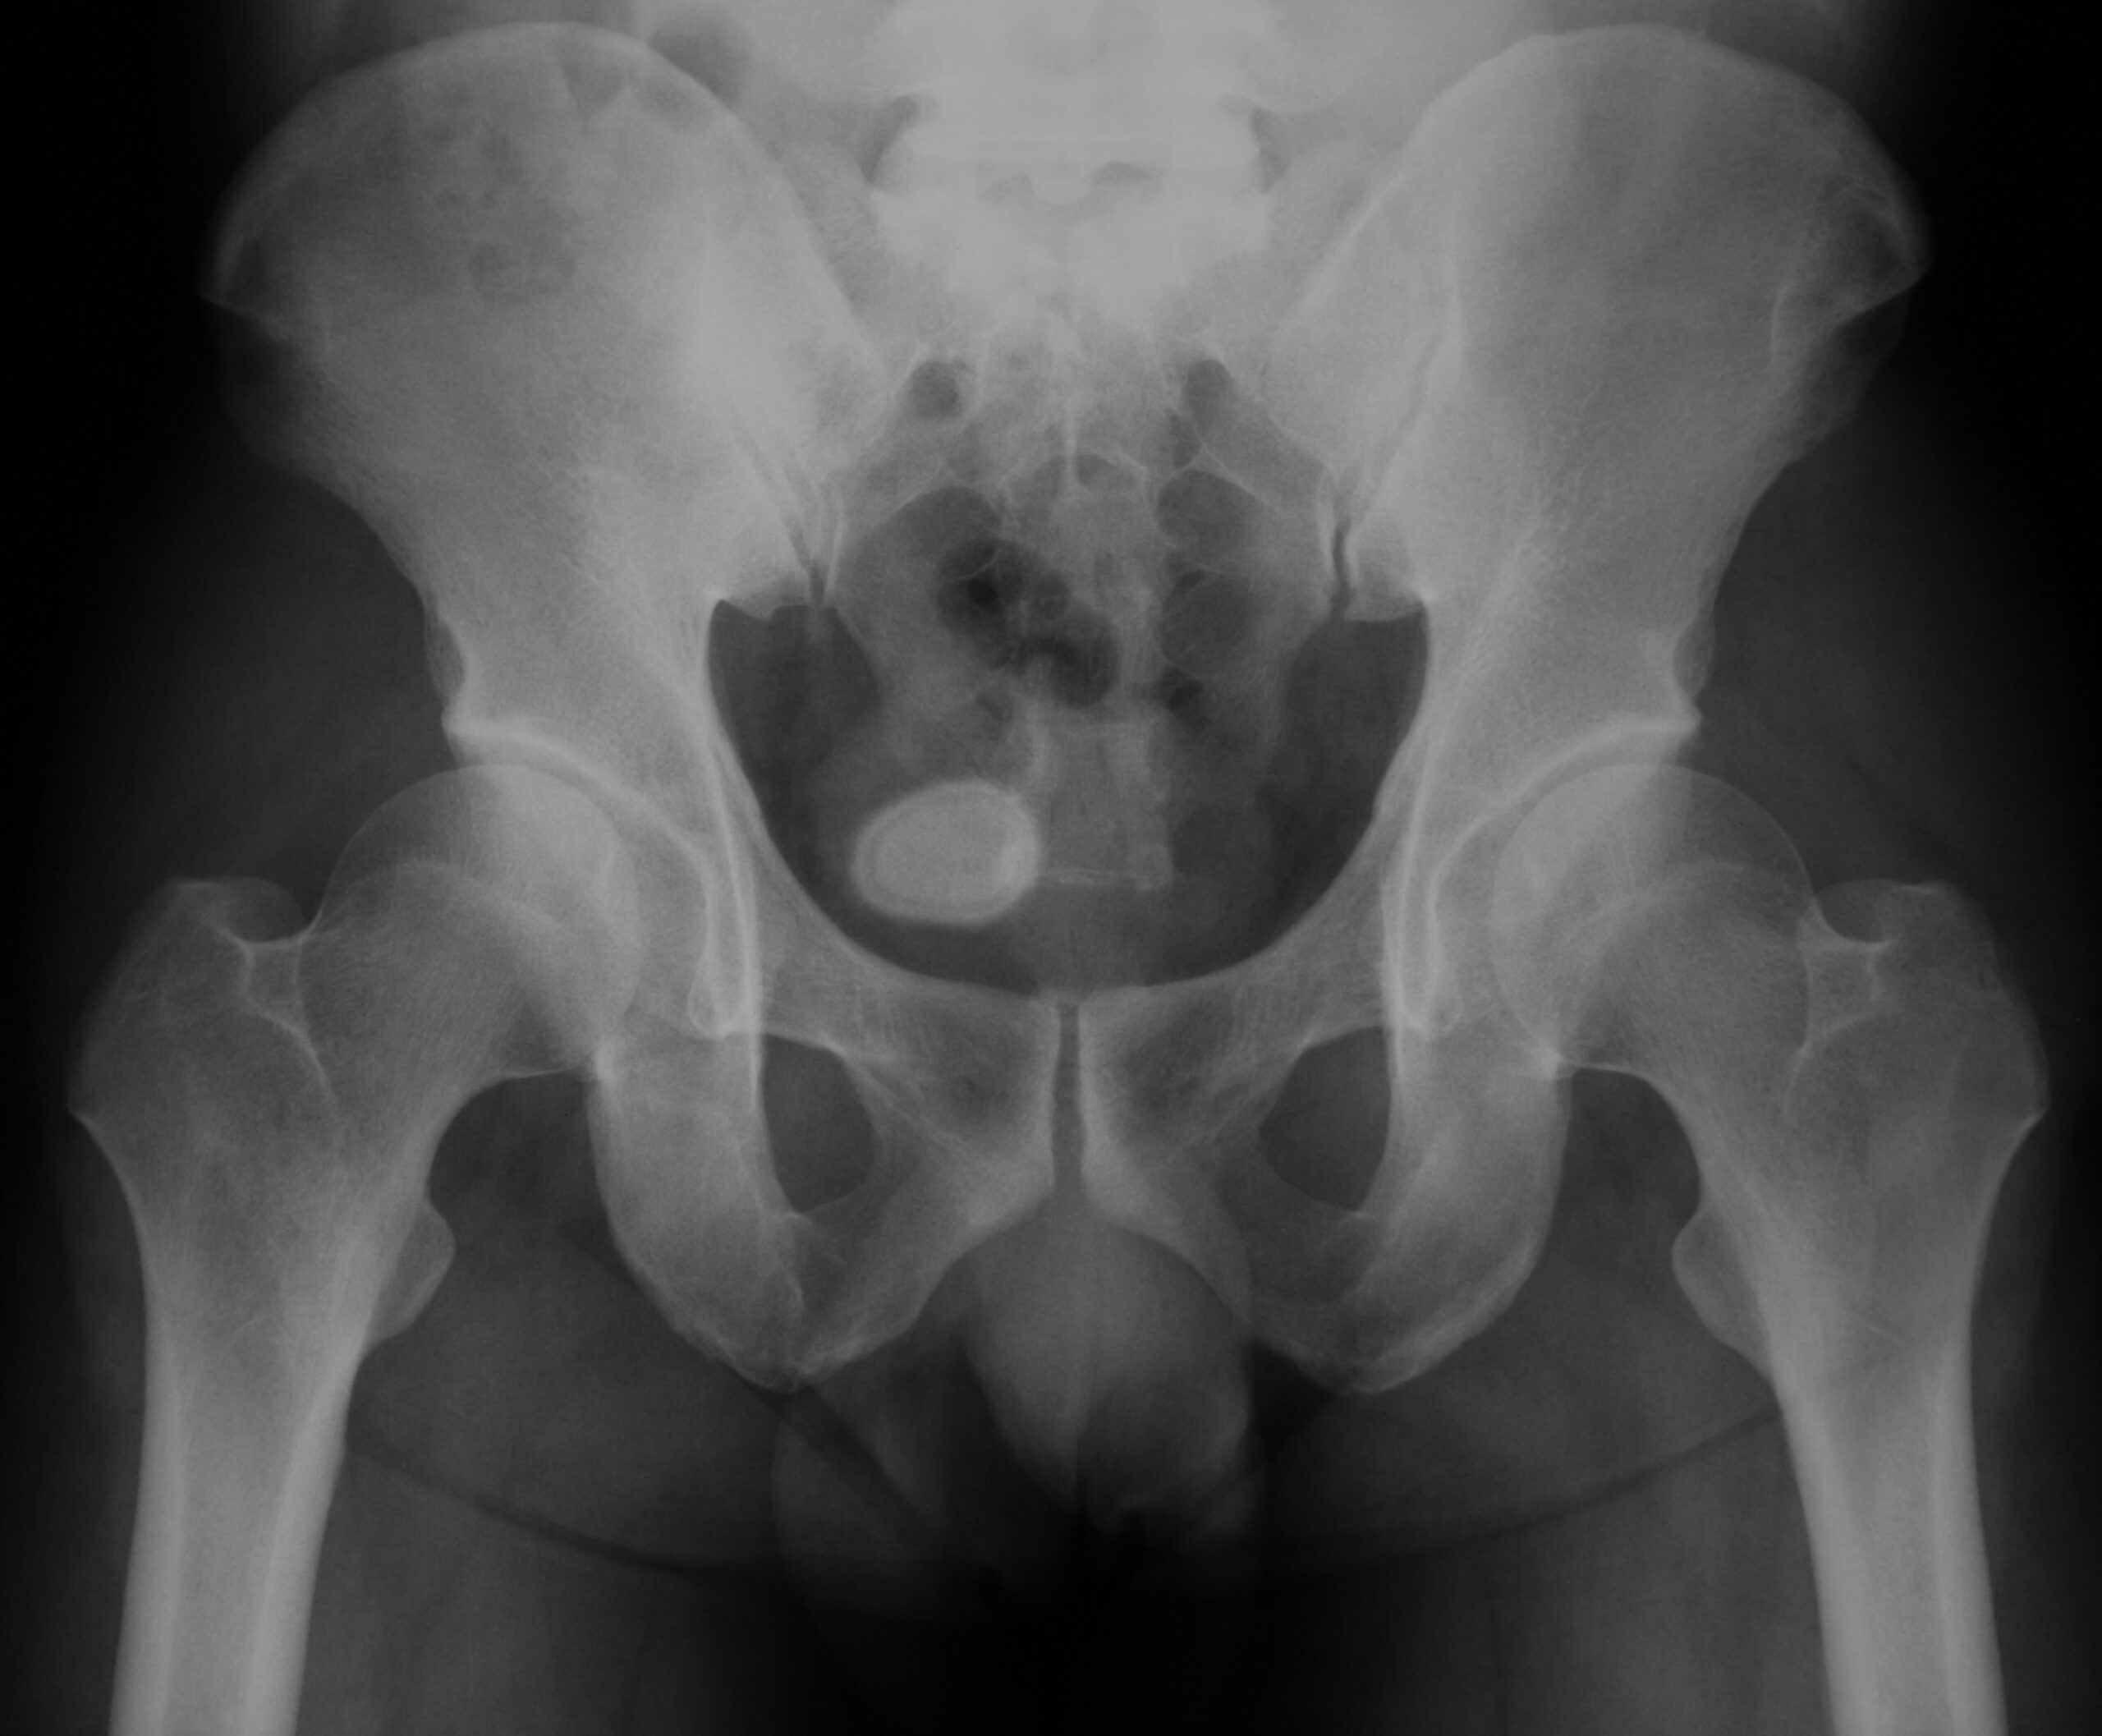

• imágenes de diagnóstico de la pelvis (tomografía computarizada, radiografía, ecografía);

• imágenes de diagnóstico del tracto urinario (tomografía computarizada), que pueden incluir material de contraste, una tinta especial que se inyecta en las venas para visibilizar los cálculos;